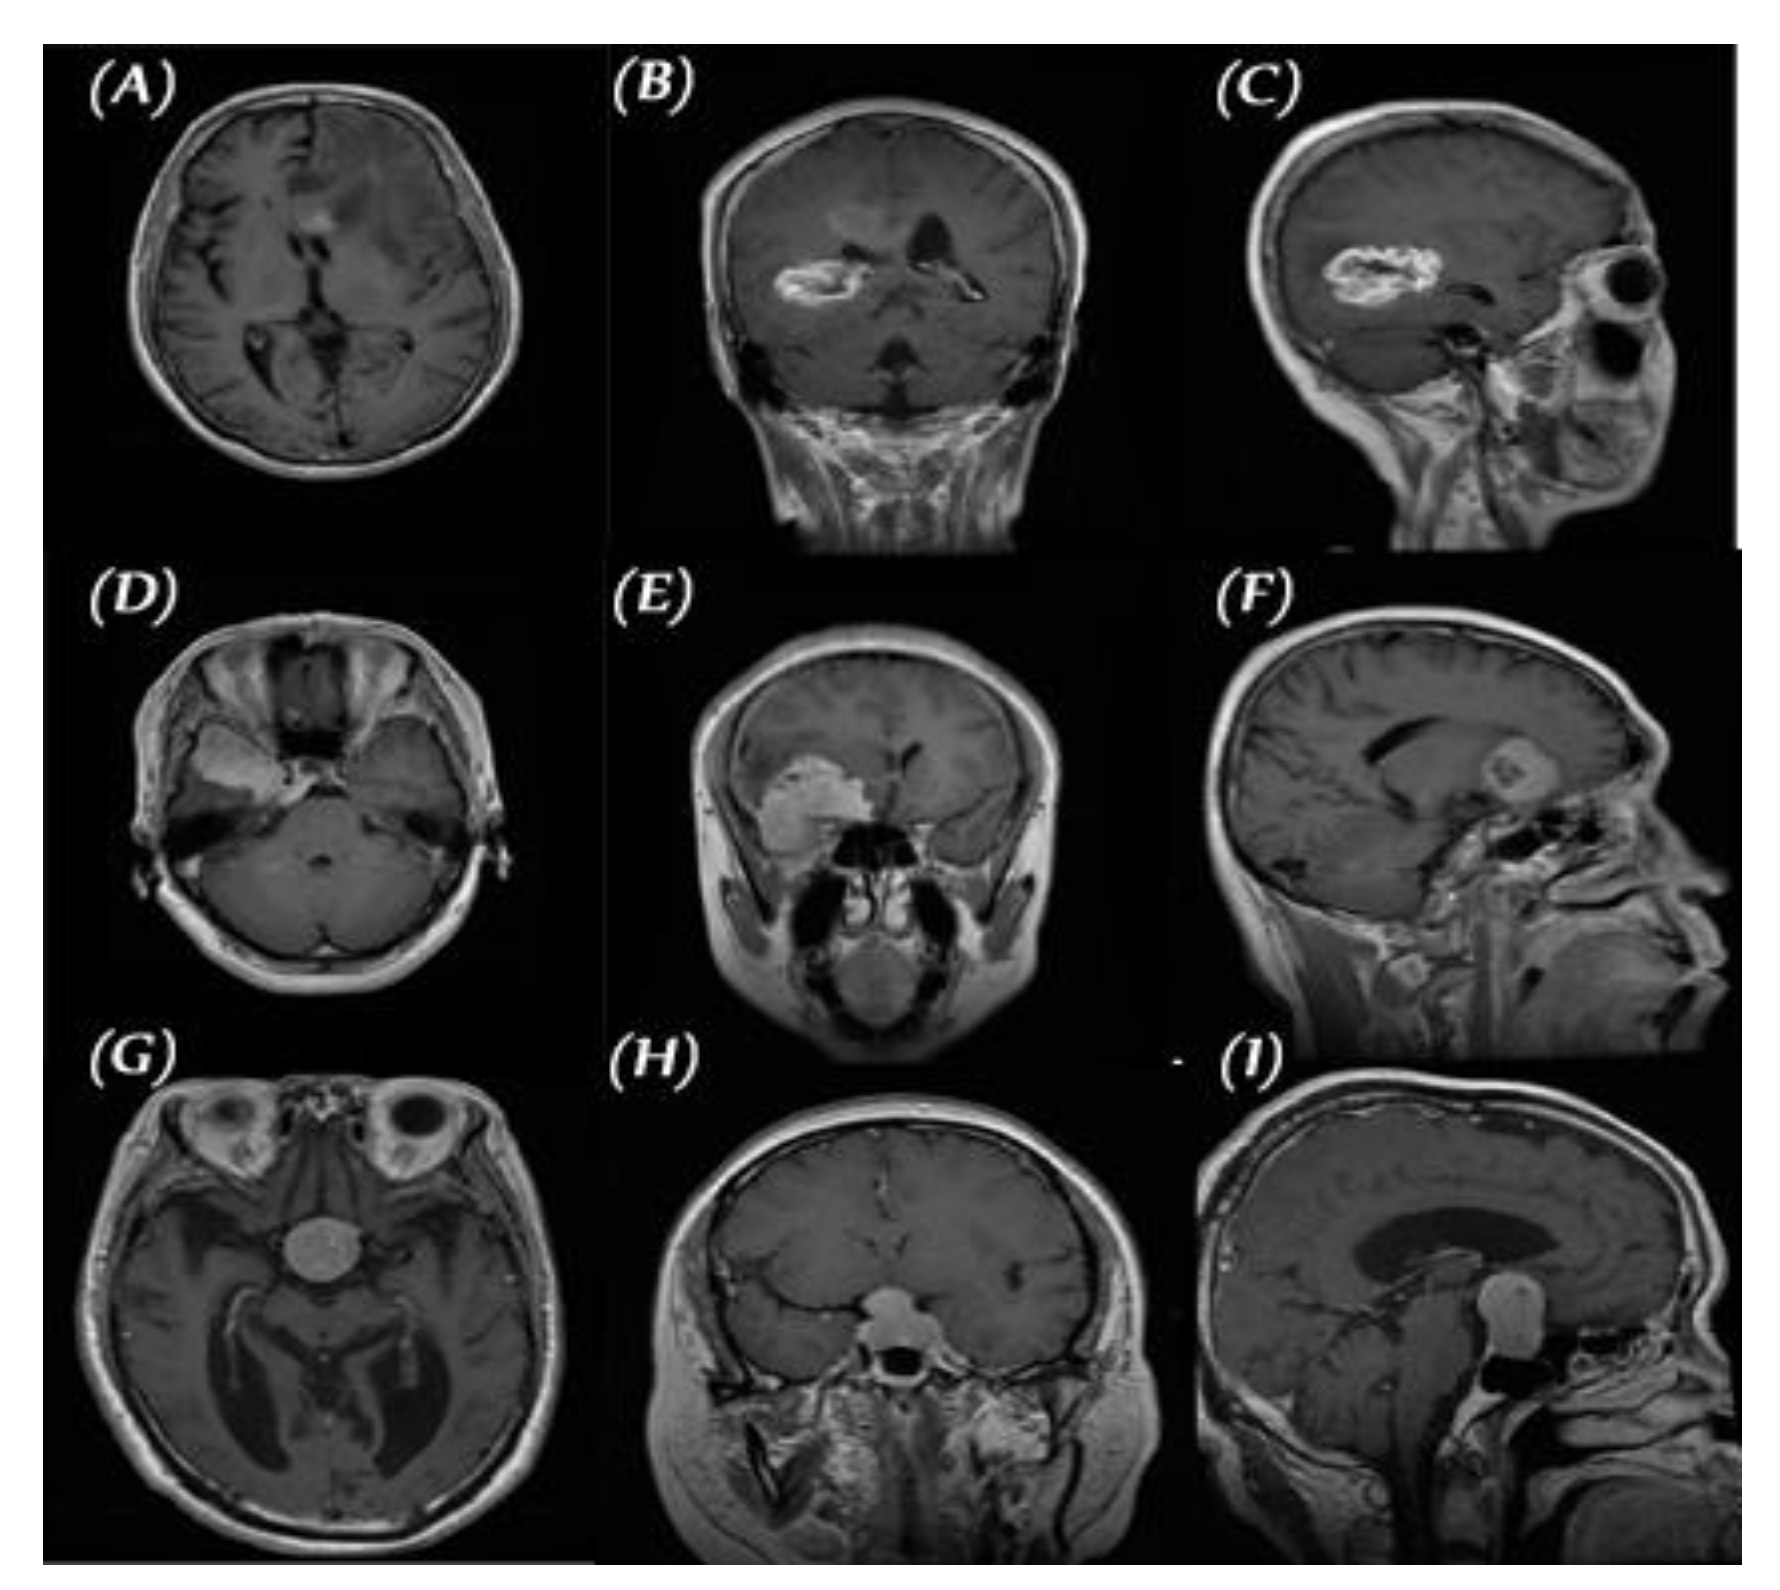

2.1. Data set for the Study